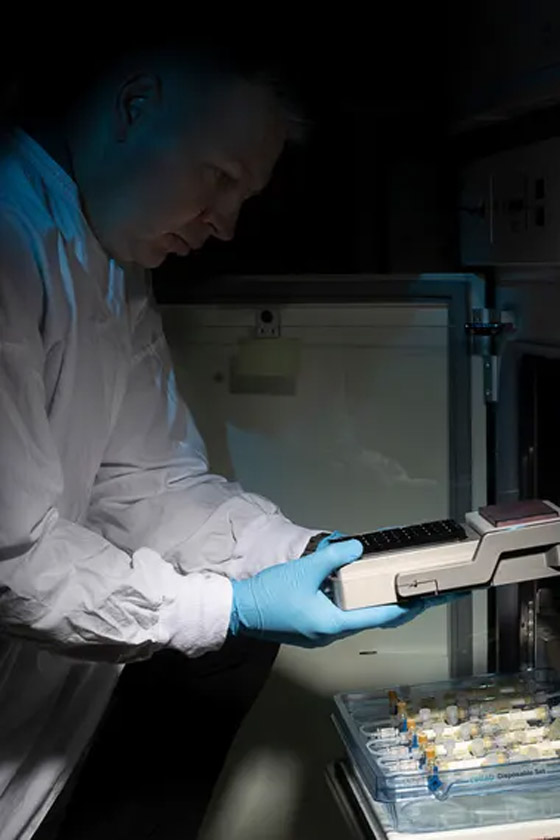

الرئتان اللتان يبلغ عرضهما بضعة ملليمترات فقط، تشبهان رئتي البشر بدرجة طفيفة. وهما موضوعتان في أنبوب بلاستيكي، وعند النظر إلى داخل هذا الأنبوب من أعلى، تبدوان مثل قطعة هلام صغيرة تنتشر في غشاء رقيق. حيث قال شرزانوفسكي: "من الضروري أن نتأكد من نمو الرئتين بما يكفي لتكونا جاهزتين وناضجتين للتجارب، لذلك طوّرنا أقطاباً كهربائية توضع باستمرار فوق نماذج الرئتين، وتراقب الإشارات الكهربية الحيوية لهما".

كما أوضح أنه بناءً على هذه الإشارات "يمكننا أن نتعرف على نضج الرئتين وجاهزيتهما لبدء التجارب. وهذا يشبه توصيل جهاز للمريض ومراقبة دقات قلبه، ولذا فهذا المستشعر الحيوي الذي طوّرناه يساعدنا أيضاً في ملاحظة، مثلاً، متى يكون العلاج فعالاً ومتى تتجدد الرئة المصابة".

كما قال إن كل رئة تحتاج إلى 28 يوماً لتنمو في المختبر، "ولم يكن الوصول إلى هذه المرحلة سهلاً، وقد استغرقنا سنوات للوصول إليها، ولتصنيع هذه الأقطاب الكهربائية". أضاف: "ولكن فيما يتعلق بتصنيع هذه النماذج فأي شخص لديه المهارات الأساسية في زراعة الخلايا سيتمكن من صنعهما. بإمكان طلاب جامعيين إدارة مختبر لتصنيع هذه النماذج، فنحن في طريقنا لحقبة يتوقف فيها إجراء الأبحاث على الحيوانات، والناس والحكومات وشركات الأدوية تعي ضرورة الاستثمار في هذا".